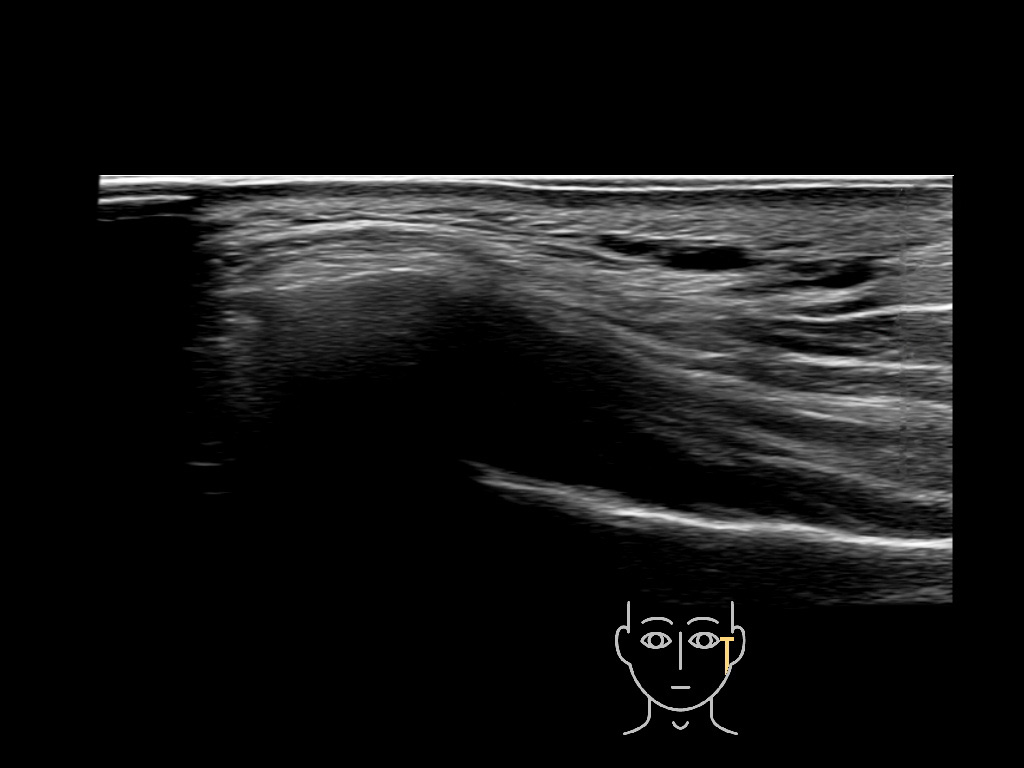

Filler deposits may end up unintentionally in the SMAS or fascial layers of the skin. Very often this will not lead to adverse events, however, adverse events ( nodules, migration / redistribution impaired muscle movement and smiling and malar edema) are are often related to filler ending up in the SMAS or fascia.

Study the first image to recognize the different layers. If you are sure about the layers, swipe to the second image to view the answer (if applicable).